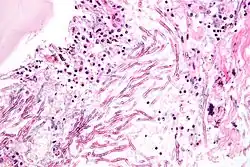

Асперги́лл, также асперги́ллюс (лат. Aspergillus), — род аэробных плесневых грибов из отдела аскомицетов. Включает несколько сотен видов, распространённых по всему миру в различных климатических условиях. Аспергиллы хорошо растут на различных субстратах, образуя плоские пушистые колонии, вначале белые, а затем, в зависимости от вида, разной окраски, связанной с метаболитами гриба и спороношением. Мицелий гриба очень сильный[прояснить], с характерными для высших грибов перегородками.

Виды аспергилл важны с медицинской и коммерческой точки зрения. Отдельные виды могут инфицировать человека и других животных. Некоторые инфекции, найденные на животных, изучались годами; в то время как другие виды, найденные на животных, описывались как новые и специфические для исследуемого заболевания. Иные были известны как уже использующиеся названия для организмов, таких как сапрофиты. Более 60 видов аспергилл являются существенными медицинскими патогенами[4]. Существует целый ряд заболеваний человека, таких как инфекция наружного уха, поражения кожи и изъязвления, классифицируемые как мицетомы.

Некоторые виды аспергилл вызывают серьёзные заболевания у людей и животных. Наиболее часто патогенность проявляют виды A. fumigatus и A. flavus, производящие афлатоксины, которые одновременно являются и токсинами, и гепатоканцерогенами. Они могут заражать пищу, например, орехи, семена и зерно. Распространёнными возбудителями различных аллергических заболеваний являются виды A. fumigatus и Aspergillus clavatus. Другие виды важны как патогены сельскохозяйственных культур. Представители рода аспергилл вызывают заболевания у многих зерновых, особенно у кукурузы; некоторые синтезируют микотоксины, включая афлатоксин.

Аспергиллёз

Аспергиллёз — группа заболеваний, вызываемых грибами рода аспергилл. Наиболее распространённый подтип инфекций придаточных пазух носа, ассоциируемый с аспергиллёзом, вызывается видом A. fumigatus[22]. Симптомы включают жар, кашель, боль в груди или диспноэ (одышку), что также проявляется и в случае многих других заболеваний и поэтому может усложнить диагностику. Обычно восприимчивы только пациенты с уже ослабленной иммунной системой или страдающие от других болезненных лёгочных состояний. Главными формами заболевания у человека являются[23][24]:

Чаще всего грибок проникает внутрь через дыхательные пути и рот и может поражать как дыхательную систему, так и центральную нервную систему, пищеварительный тракт, кожу, органы чувств и половую систему. Аспергиллёзный менингит или энцефалит в большинстве случаев заканчивается летальным исходом. Встречаются также грибковые поражения селезёнки, почек и костей аспергиллами, однако большей частью они вызваны вторичной инфекцией. Аспергиллёз дыхательных путей часто диагностируют у птиц, и известны определённые виды аспергилл, заражающие насекомых[4].